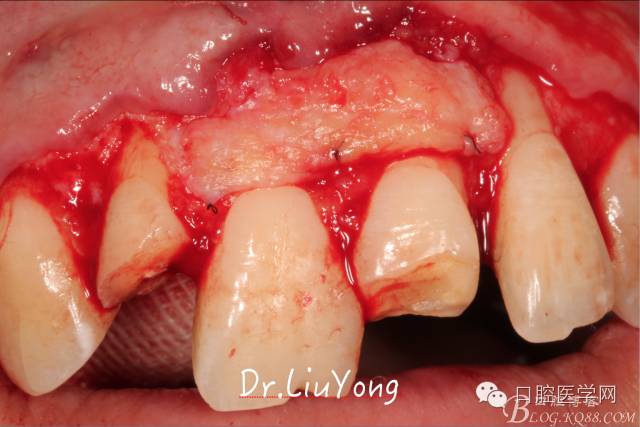

系帶手術(shù)后兩周,進行上頜前牙唇側(cè)的牙齦退縮的手術(shù)治療,由于局部附著齦缺如及牙齦厚度不足,因此同期進行上皮下結(jié)締組織移植,解決附著齦及牙齦厚度不足的問題。

術(shù)中,可見明顯的唇側(cè)骨開裂,如上圖: